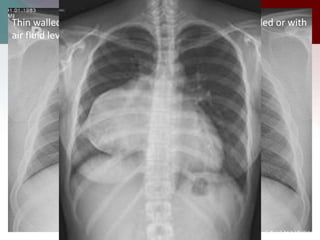

Thin walled spherical unilocular masses –fluid filled, air filled or with

air fluid levels

Thin walled sphericalunilocular masses –fluid filled, air filled or with air fluid levels